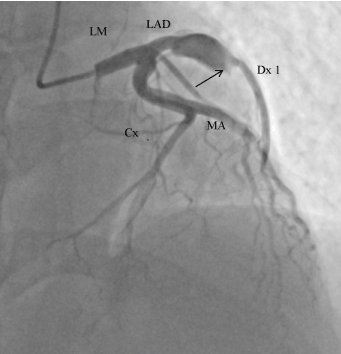

We present the case of a 40-years-old male, irregularly treated for arterial hypertension, with history of nicotinism, with no burden of family history of cardiovascular problems, admitted to the Cardiology Clinic because of STEMI of the anterior wall, in the 6th hour after onset of pain. The patient for the first time in his life experienced a typical pain in the chest, lasting for two hours, with accompanying vegetative symptoms: anxiety, weakness and increased perspiration. At admission the patient was in overall relatively good condition, with sufficient circulation and respiration, with increased blood pressure of 160/100 mmHg, SO2 98%; in ECG - steady sinus rhythm 74 bpm, QS complexes in V1-V4, with ST elevation by 2 mm in V2-V4. Markers of myocardial necrosis were increased: TnT 2.17ng/mL (normal range up to 0.014 ng/mL), CKMB 138 ng/dL (normal range up to 4.87 ng/dL). Coronarography performed in urgent mode demonstrated obstructed left anterior descending artery (LAD) and aneurysm of its proximal segment (Figure 1). In the right coronary artery (RCA) an ectasia was observed, involving its third segment (Figure 2). Restoration of patency of LAD was attempted, but was unsuccessful. Conservative treatment of acute coronary syndrome was implemented, according to the typical scheme. Considering long time passed since the onset of pain, a fibrinolytic treatment was not used. Control echo of the heart performed at rest demonstrated apical hypokinesia of the inferior wall, anterior wall and interventricular septum; the global ejection fraction was 52%. On the 8th day of hospitalisation the patient had exercise echocardiography performed, demonstrating improved contractility of hypokinetic segments of the left ventricle. The patient was qualified for aortic-coronary bypass grafting of the closed LAD, using the MIDCAB method.

Figure 2. Right coronary artery ( RCA). The arrow shows ectasia of the third segment